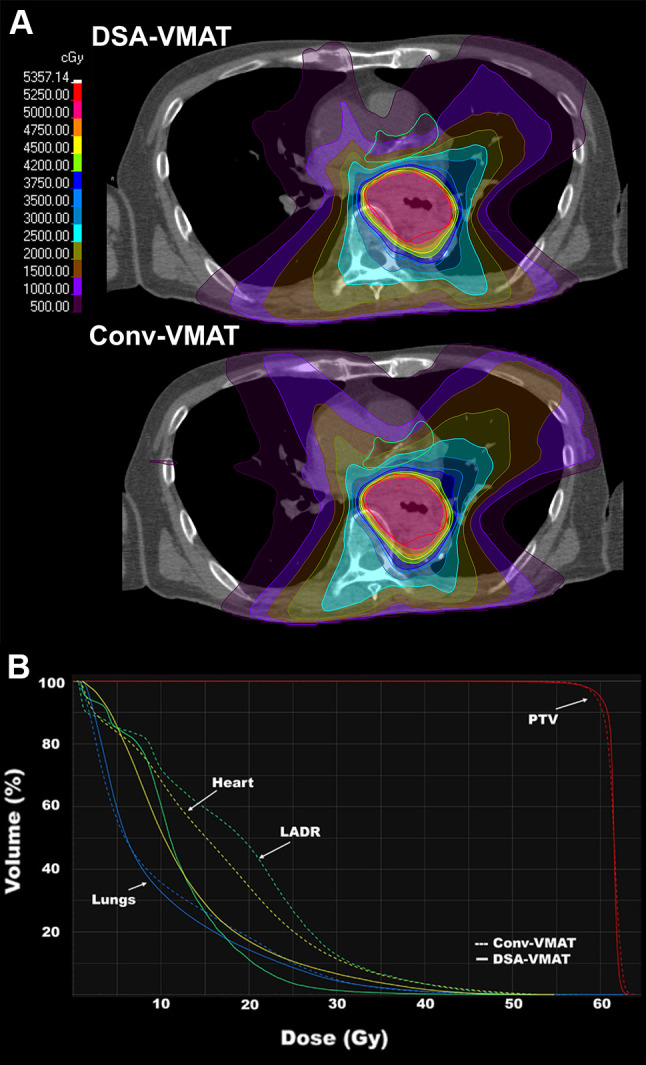

Background/aim: The dose to the left anterior descending coronary artery (LAD) is associated with mortality in patients with esophageal cancer (EC) who underwent radiotherapy. The aim of this study was to compare the dose distributions to the LAD region achieved through volumetric-modulated arc therapy (VMAT) planning using a dynamic swing arc in OXRAY (DSA-VMAT) and conventional coplanar (Conv-VMAT) planning.

Patients and methods: Ten patients with EC who had undergone radiotherapy (60 Gy in 30 fractions) at our Institution were selected for inclusion in the study. Two virtual plans (DSA-VMAT and Conv-VMAT) were created to compare the dose distributions of the LAD region, heart, lungs, and planning target volume (PTV). All plans were analyzed using paired t-tests.

Results: The mean values±standard deviation for 15 Gy to the LAD region (V15) were 10.48±13.04% for DSA-VMAT and 30.28±23.56% for Conv-VMAT. Compared with Conv-VMAT, DSA-VMAT significantly improved V15 of the LAD region (p=0.01). In addition, DSA-VMAT significantly reduced the mean heart dose (8.64±5.37 vs. 11.23±7.37 Gy), heart V40 (17.55±4.76% vs. 20.44±6.06%), lung V20 (14.87±5.93% vs. 17.81±7.70%), and lung V5 (57.27±8.24% vs. 61.15±9.97%) compared to Conv-VMAT (all p≤0.01). In contrast, there were no significant differences between the two groups in PTV dose coverage [D95 (p=0.61), D50 (p=0.62)], or conformity index (p=0.91).

Conclusion: Compared with Conv-VMAT, DSA-VMAT improved the dose distribution of the LAD region without impairing the PTV dose coverage. Thus, DSA-VMAT may reduce radiation-induced heart disease in patients with EC without loss of efficacy.